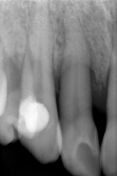

Il trattamento è stato eseguito su una paziente di sesso femminile con una grave mobilita di III grado di un 1.2 (incisivo laterale). Purtroppo la paziente fumatrice ha avuto un aggravamento della situazione nel corso degli anni, anche dopo curettaggi a cielo copero e scoperto.

In collaborazione con la Dott.ssa Laura Marchione siamo intervenuti con un innesto di osso eterologo ( Osteo-Biol) Gen-Oss mischiato con Gel 40 e ricoprendo l'innesto con una membrana riassorbibile della Osteo-Biol. Notate il risultato ed il recuprero della profonda tasca a 4 e poi a 9 mesi. Il risultato è ottimale e la mobiltà scomparsa. Non so quanto durerà, la paziente è ancora una fumatrice convinta!